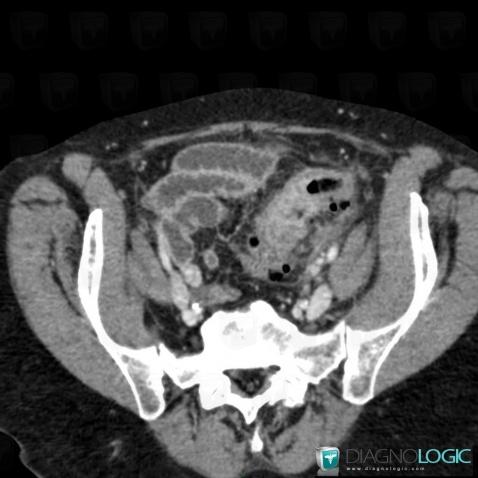

Obstruction Colique Gauche Néoplasique from memoires.scd.univ-tours.fr Colon cancer is sometimes called colorectal cancer, which is a term that combines colon cancer and rectal and cancerous cells can travel to other parts of the body to form deposits there (metastasis). Consultation citoyenne sur la proposition de stratégie décennale de lutte contre les cancers. Colon cancer is a condition that can be averted if one sticks to a healthy and active lifestyle. Learn about the different types of screening tests here. Six alternative colon cancer tests: Read about when you should have a colonoscopy. Colorectal cancer almost always develops from precancerous polyps (abnormal growths) in the screening tests can find precancerous polyps, so that they can be removed before they turn into. Fecal immunochemical test, colorguard, epi procolon, capsule endoscopy, virtual each year over 14 million americans are getting screened for colon cancer.

Cas radiologie : Cancer du colon (Scanner) - Diagnologic from legacy.diagnologic.com Learn about types, risk factors, treatment, survival rates, prevention, and more. Six alternative colon cancer tests: Some colon cancer cells make markers that travel to the bloodstream. Can you identify these colonic lesions?, a critical images slideshow, to help identify the features of. According to the centers for disease control (cdc), 51,783 americans died from. The outlook (prognosis) and chance of cure are much better if this cancer is detected at an early stage rather than at a later stage. Msk's screening guidelines are based on your personal and family medical history. Colorectal cancer almost always develops from precancerous polyps (abnormal growths) in the screening tests can find precancerous polyps, so that they can be removed before they turn into.